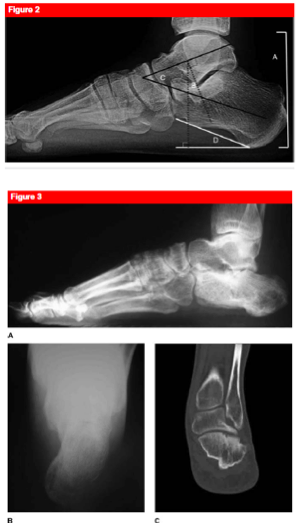

What are the typical radiographic measurements of a calcaneus fracture

A

• Bohler angle (normal is 25-40 degrees)

• flattening represents collapse of the posterior facet

• drawn by connecting

• anterior process

• highest point on posterior articular surface

• superior tuberosity

• Gissane angle (normal is 130-145 degrees)

• an increase represents collapse of posterior facet

• Harris view

• allows visualization of subtalar joint

• comminution, degree of varus

• l_oss of height_, widening, and impingement on peroneal space

• take with foot maximally dorsiflexed and beam angled at 45 degrees

• Broden views

• allows visualization of posterior facet

• ankle internally rotated 40 degrees and ankle in neutral dorsiflexion. Views taken at 10, 20, 30, 40 degrees

• largely replaced by CT scan